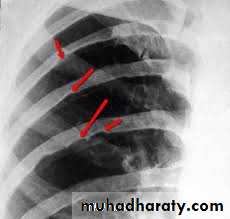

In older children: the ECG and chest x-ray usually show LVH and a mildly enlarged heart. Rib notching may also be seen in older children (>8 years of age) with large collaterals. Echocardiography shows the site and degree of coarctation, presence of LVH, and aortic valve morphology and function.

3 sign of aorta Rib notching